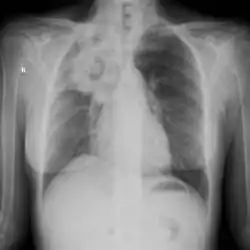

The extent of infection may be seen on X-ray or CT scan. On chest X-ray and CT, pulmonary aspergillosis classically manifests as a halo sign, and later, an air crescent sign.[21]

Large cavity mass lesion seen right upper lung